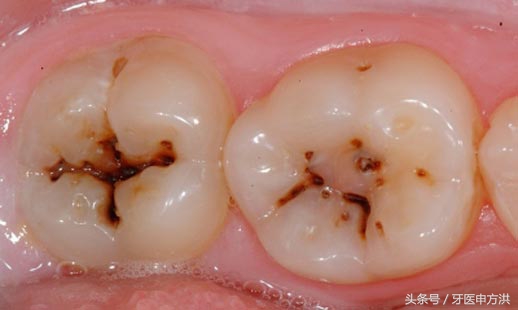

看得见的一般是静止龋或慢性龋,通常呈黑褐色,质地较干硬,这种龋坏的速度比较慢,属于慢工出细活的类型。

看不见的就是急性龋,多见于儿童和青年人。通常呈白色或者米黄色,质地湿软,这种龋坏速度异常快,没一会功夫就能把你的牙齿钻个底朝天。

一般来说,一颗牙齿从发现小黑点,任其开展就会构成明显的蛀洞,到整颗牙齿蛀坏。粗线条的将成人蛀牙呈现时间计算,牙齿从白垩变--墨染--龋坏普通是需求1-2年时间,蛀牙开展到牙髓炎(蛀牙攻破牙实质进入牙髓)普通需求3-4年。假如蛀牙伤及牙髓你还无动于衷的话,那离拔牙/牙齿零落不远了,同时,你还要忍耐疼痛担负更多的治疗费用,得失相当。